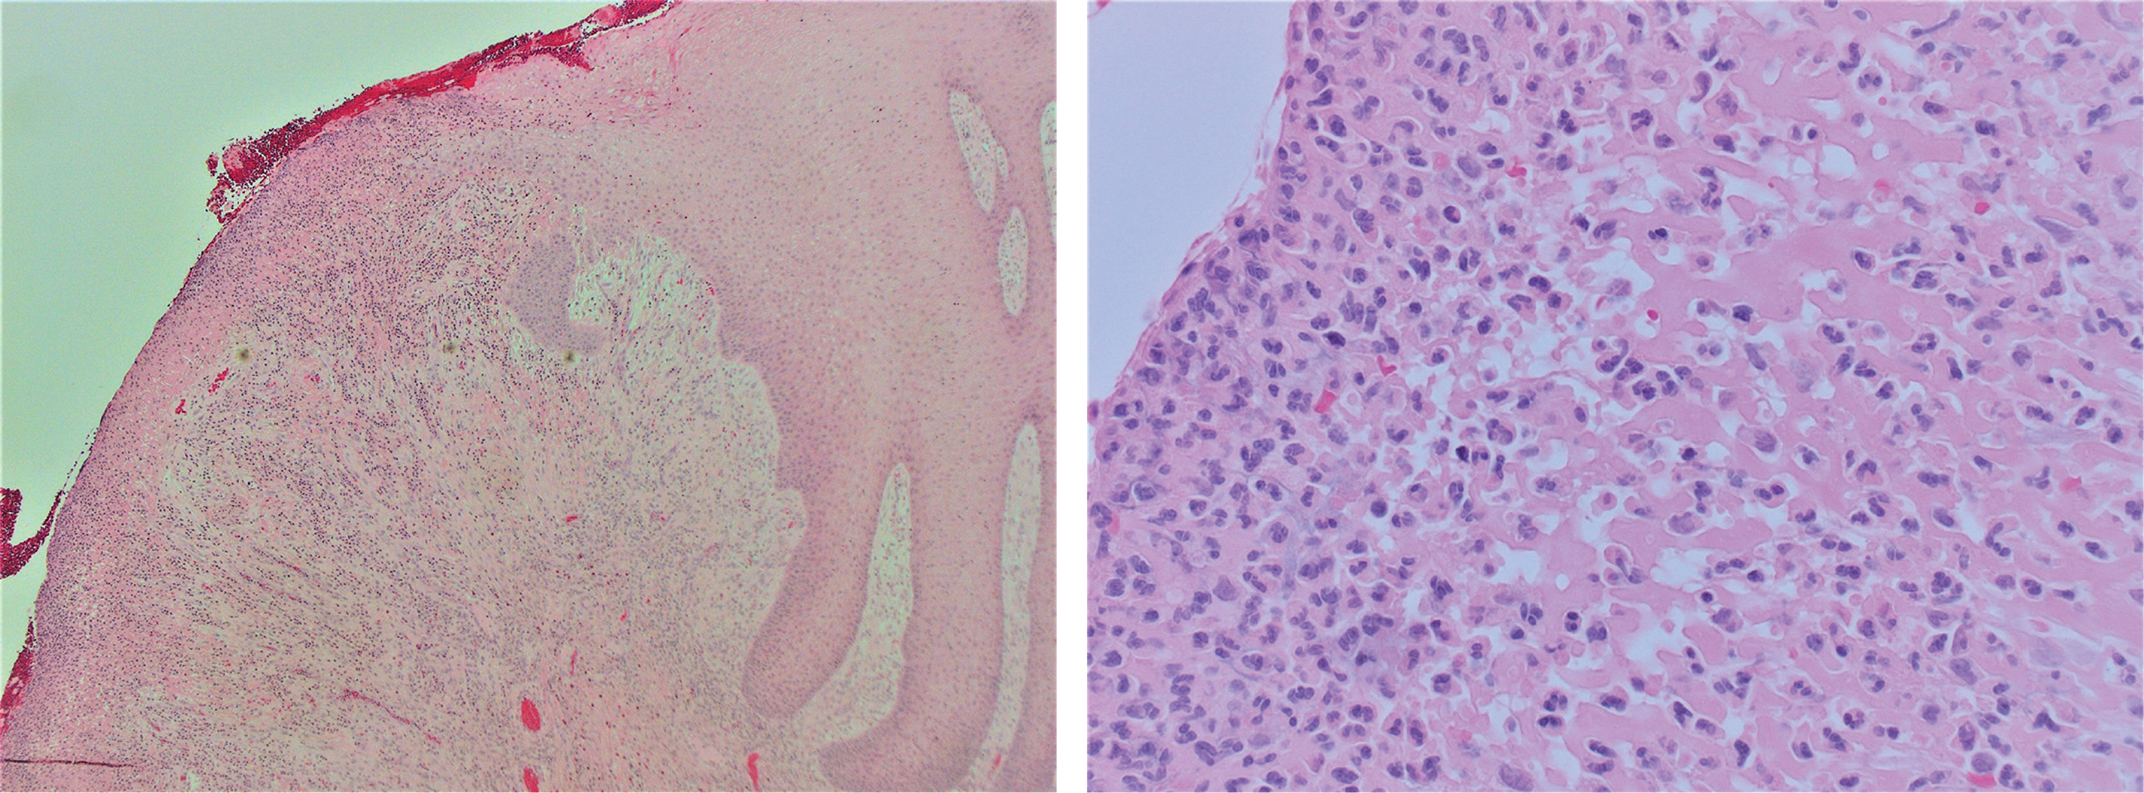

An IgG-immunostaining was performed, a method that can be unreliable and difficult to interpret due to high-background staining (Figure 9a). As a result, accurate IgG4/IgG ratios are sometimes difficult to obtain (30, 31). In our case, the IgG-immunostaining was performed on the two larger biopsies. In both samples, ≥ 71% of the IgG-positive plasma cells expressed IgG4 (Figure 9b), that is, an IgG4+/IgG+ ratio of ≥ 71%, with IgG4+ plasma cells/high-power field (HPF) being 10–50. While a significant percentage of the plasma cells expressed IgG4, the patient did not have elevated levels of IgG4 in the serum. However, this parameter is not precise enough and lacks a predictive value for diagnosis (31, 32).

Fig 8

Figure 9. (a) & (b) Immunostainings for IgG (9a) and IgG4 (9b) in area under retained epithelium, both at x 400. Majority of IgG-positive plasma cells shows positive staining for IgG4.